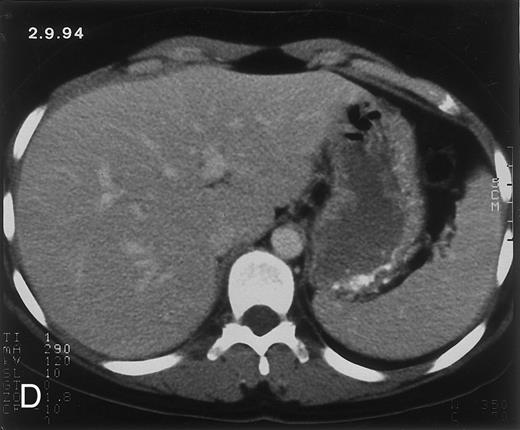

(C) On June 6, 31 days after normalization of neutrophils, CT again shows multiple lesions in the liver (arrowheads) with a different presentation: the small lesions show strong peripheral enhancement. (D) On September 2, 129 days after neutrophil recovery, all hepatic lesions have completely resolved.